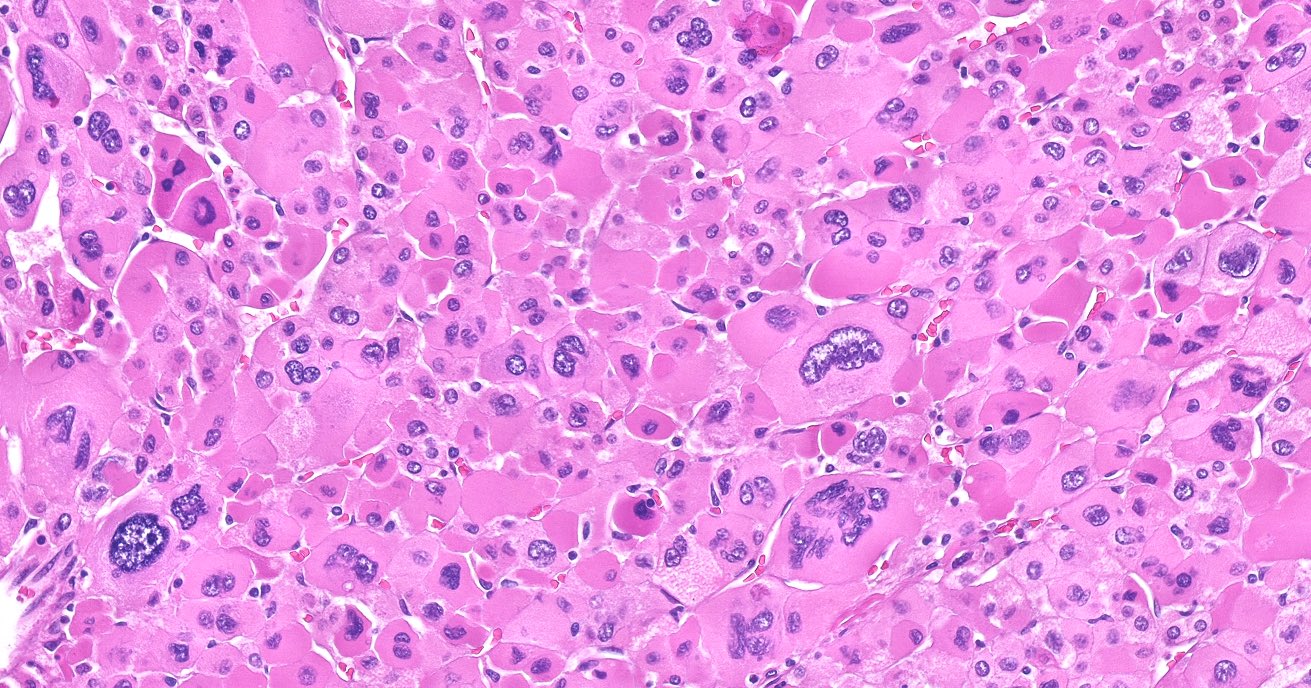

Microscopic (histologic) description

- In comparison to surrounding adrenal gland, adenoma cells are larger with different cytoplasm, increased variation in nuclear size

- Distinct cell borders, cells have abundant foamy cytoplasm reminiscent of zona fasciculata

- Balloon cells: clusters of cells with enlarged lipid-rich cytoplasm (seen in Cushing syndrome)

- Histologic variants: oncocytic, myxoid

Microscopic (histologic) images

Contributed by Xiaoyin "Sara" Jiang, M.D., Debra Zynger, M.D., @Andrew_Fltv on Twitter and @SueEPig on Twitter